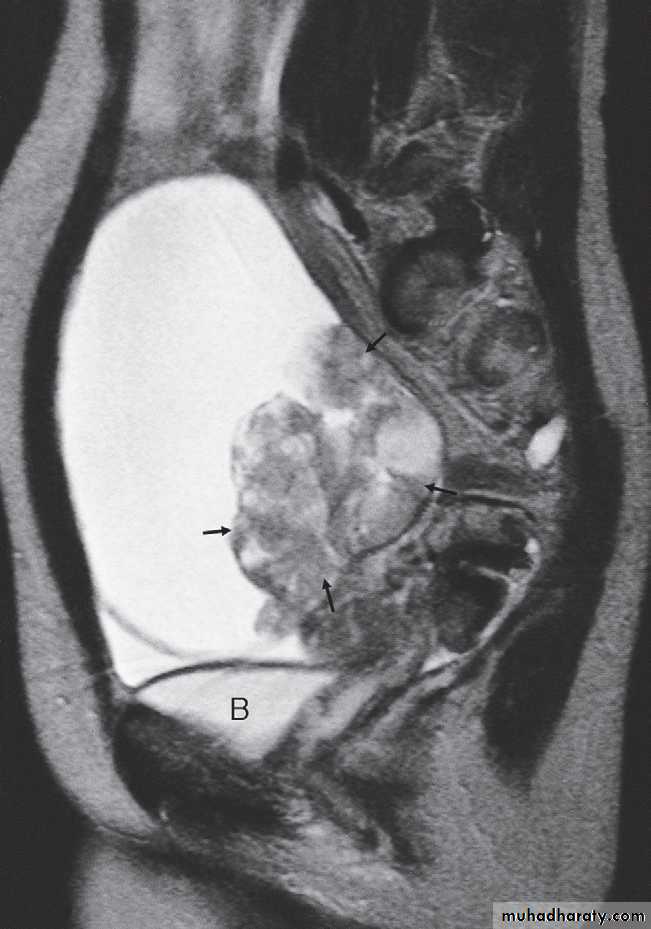

Magnetic resonance imagingPelvic anatomy is very well demonstrated because of the excellent soft tissue contrast afforded by MRI. Images are usually taken in the axial, coronal and sagittal planes . T2-weighted sagittal images show the vagina and cervix in continuity with the body of the uterus.

The zonal anatomy of the uterus is best demonstrated on T2-weighted images, with the endometrium having a high signal intensity, the adjacent inner myometrium (junctional zone) a low signal intensity, and the myometrium an intermediate signal intensity .

The cervix may be predominantly low in signal intensity.

MRI may be used to further characterize indeterminate masses as benign or malignant prior to deciding on patient management. With disseminated malignancy, deposits within the omentum and ascites may be visible .

At CT fibroids are usually the same density as the adjacent myometrium. MRI can readily identify fibroids as they typically have a different signal characteristic from the normal uterus .

On MRI, there is focal or diffuse thickening of the junctional zone and, in some cases, multiple bright projections are seen extending from the endometrium into the myometrium .